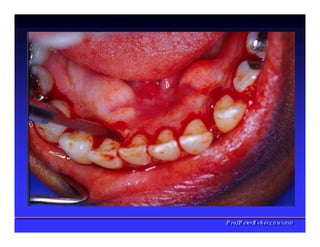

Periodonto de Proteção

✓Divisão Topográfica

1. Gengiva livre

2. Gengiva inserida

3. Mucosa alveolar

4. Papila interdentária

✓Gengiva livre

➢ Colar com cerca de 0,5 a 2,0 mm de altura

✓Gengiva inserida

➢ Firme, resistente e

inserida ao periósteo

do osso alveolar

➢ Limitada pela gengiva marginal livre e

mucosa alveolar

✓Mucosa alveolar

➢ União frouxa ao tecidos

➢ Altamente vascularizada

➢ Móvel, ausência de pontilhado

➢ Ausência de queratina na superfície